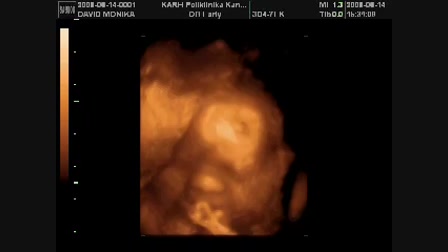

Rozi & Kyra kutyus

Date: 2008. 09. 23.

Tags: családgyerek